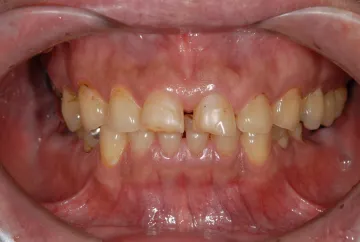

初診時

| 患者様のお悩み | 外傷で歯が抜けた |

|---|---|

| 治療法・使用素材 | インプラント治療の後、セラミック治療 |

| 患者様の年代 | 20代 |

| 治療開始年齢 | 20代 |

| 治療にかかった期間 | 8か月 |

| 性別 | 女性 |

| この治療のリスクについて | インプラントが正しい位置に入るかどうか |

| 治療にかかった費用 | 45万円 |